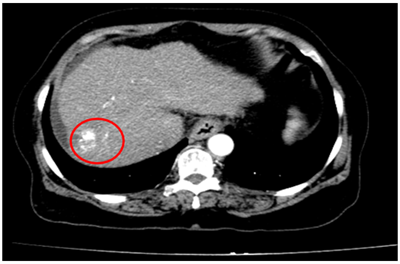

Ca lâm sàng:Hiệu quả điều trị đích bằng Osimertinib ở bệnh nhân UT biểu mô tuyến của phổi giai đoạn IV có đột biến gen EGFR L858R (Exon 21) tại Trung tâm YHHN&UB-Bệnh viện Bạch Mai

Ung thư phổi là một trong những ung thư có tỷ lệ mắc và tử vong cao nhất trên toàn thế giới. Theo GLOBOCAN 2022, ung thư phổi đứng thứ hai về số ca mắc mới với khoảng 2,5 triệu trường hợp mỗi năm và là nguyên nhân hàng đầu gây tử vong do...